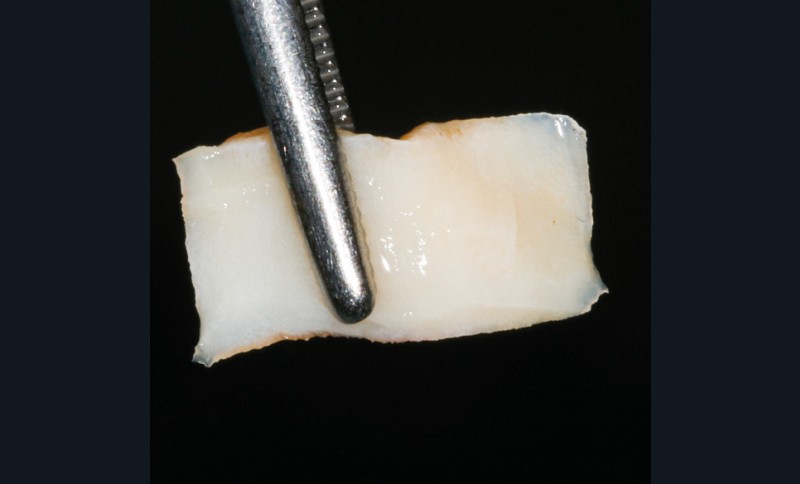

- Parmi ces longueurs d’onde, deux lasers (Er-YAG et Diode) sont intéressants dans le traitement de la péri-implantite :

– Le laser Er-YAG, utilisé pour le nettoyage, est un laser avec un milieu actif composé d’yttrium, d’aluminium et de grenat dopé à l’erbium. Avec une longueur d’onde de 2 940 nm situé dans l’infrarouge, le laser Er-YAG est un laser à haute énergie, dont la lumière est absorbée dans l’eau et dans l’hydroxyapatite et qui ne pénètre pas profondément. Ceci permet de couper des tissus mous et des tissus durs, mais également de désorganiser le biofilm bactérie.